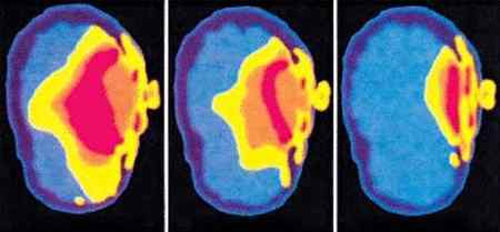

Ci-dessus vous verrez une image d’une étude publiée par le Dr Om Gandhi, de l’Université de l’Utah en 1996 (publication de l’IEEE). Voici une autre de ses publications quelques années plus tard qui cite également la photo ci-dessus. À l’extrême gauche, vous verrez comment le rayonnement du téléphone cellulaire, à ce moment-là, a affecté le cerveau d’un enfant de 5 ans, au milieu, le cerveau d’un enfant de 10 ans, et à l’extrême droite, le cerveau d’un adulte. Le cerveau d’un enfant absorbe plusieurs fois plus que celui d’un adulte.

Ces pays n’interdisent pas le WiFi pour rien. La science est très claire et parle d’elle-même. Il existe des milliers d’études évaluées par des pairs qui révèlent des préoccupations multiples, des liens avec le cancer et bien d’autres choses encore. Et c’est particulièrement inquiétant pour les enfants parce que la moelle osseuse de la tête d’un enfant absorbe 10 fois plus de radiation que celle d’un adulte.